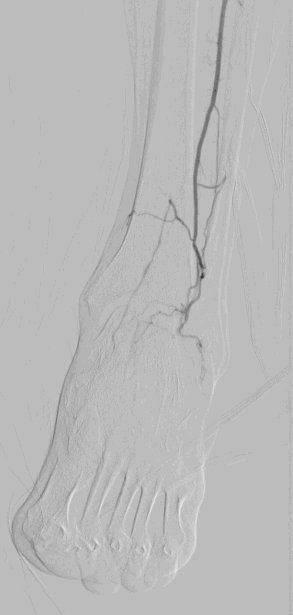

手术过程(三):左膝下胫前、胫后动脉全程闭塞;足底弓狭窄闭塞;应用雅培Command-18导丝成袢技术依次开通胫前及胫后,分别应用雅培Armada球囊2.0mm×200mm球囊扩张,再使用2.5mm×200mm药涂球囊扩张胫前动脉和胫后动脉

图片

术前

术后